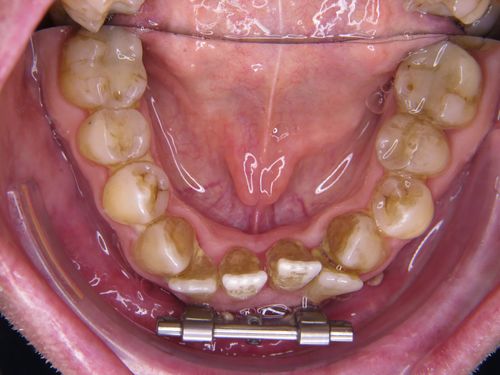

In einem ersten Behandlungsschritt wurden Ober und Unterkiefer verbreitert (transversaler Erweiterung). Allein dadurch zeigte sich schon eine Verbesserung der Atmung im Schlaf.